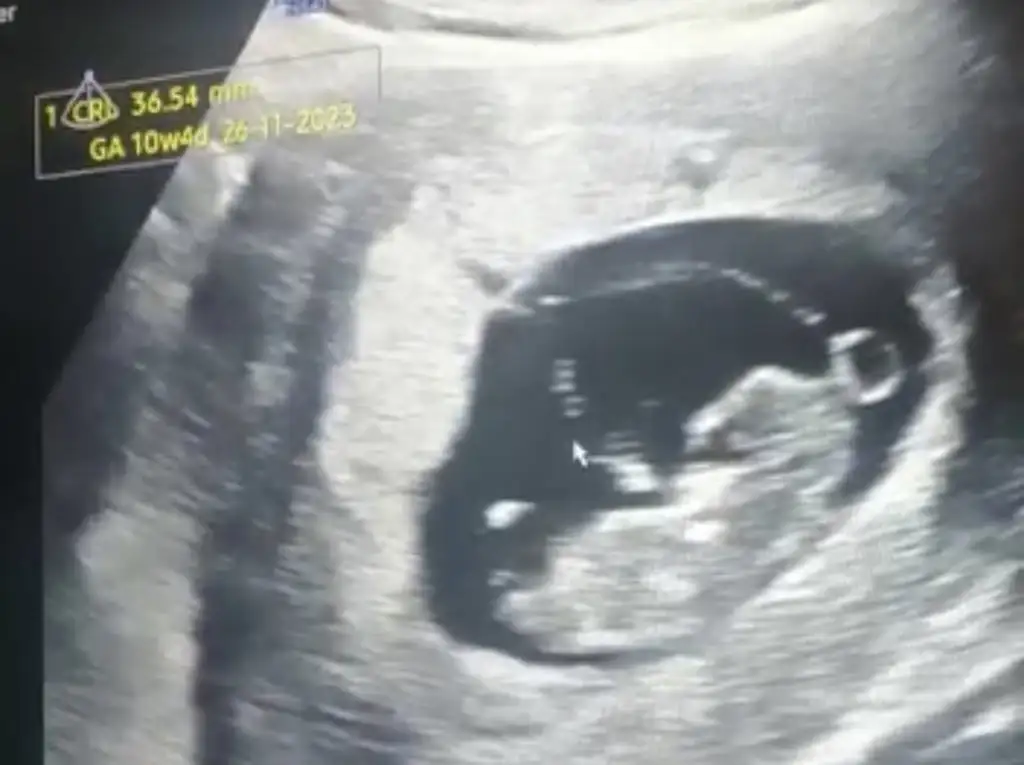

Ayyy olsun kalitesiz falan bebiş fotosu bebiş fotosudur :) Nubu görmeye çalışıyorum ama başaramıyorum :)

nubu birazdaha belli olsa iyiymis.nekadar buyumus masallah ya

Kocaman oldu bunlaaarrrr

Bence bebeği gördüğümüze dua edelimnubu birazdaha belli olsa iyiymis.nekadar buyumus masallah ya